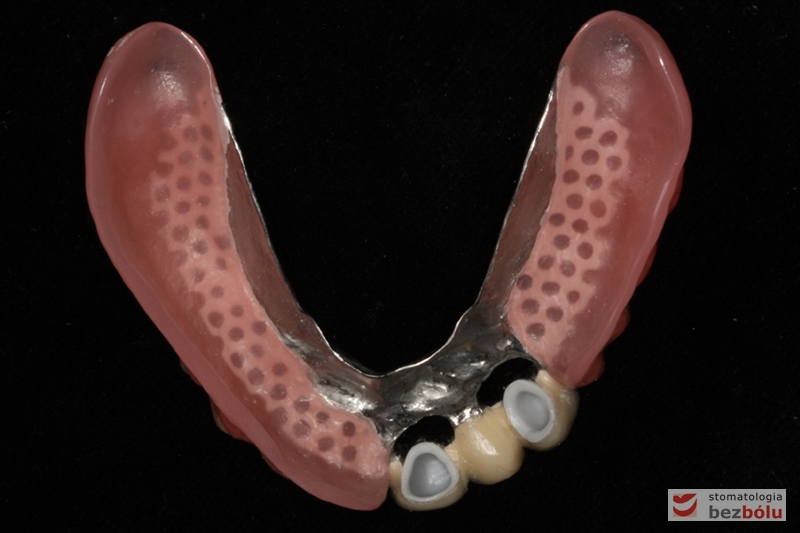

Odbudowa protetyczna żuchwy - wykonana przy użyciu zębów Michał Anioł Integrale

Odbudowa protetyczna żuchwy – wykonana przy użyciu zębów Michał Anioł Integrale